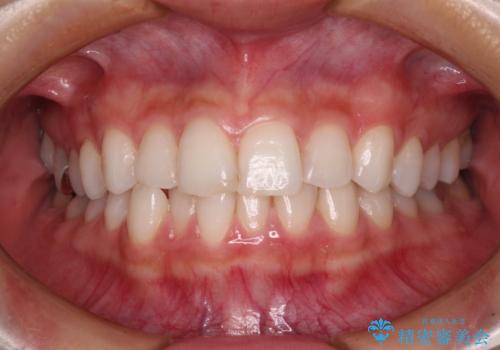

- 歯並びと虫歯をきれいにしたいとのことで来院された患者様です。

楽して短期間で歯列を整えたいとのことで、ワイヤー装置を用いて矯正治療を行い、矯正治療後に下顎の虫歯はセラミックインレー、上顎はPGAインレー(ゴールドインレー)、根管治療を行う歯についてはオールセラミッククラウンにて補綴治療を行うこととしました。

- 20代女性

矯正治療は8ヶ月ほどで終了し、速やかに虫歯治療に移行することができました。